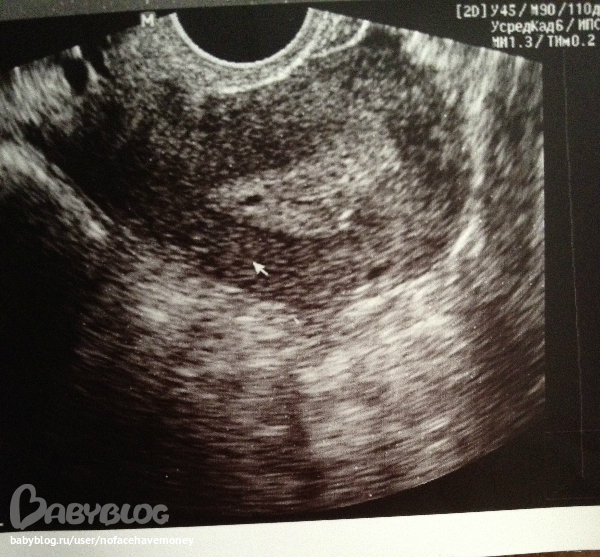

затем мы с ней прошли к узисту и вот смотрите какое заключение(((

пока особо не видно плодного яйца, но что то есть-но не поймут то ли плодное яйцо то ли нет

на фото видна точечка ,вы видите ?узист сказала если это беременность-то плодное яйцо слишком снизу находится чуть ли не рядом у входа шейки матки